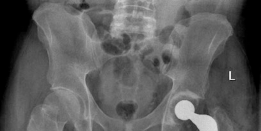

Radiographic Confirmation

Postoperative AP pelvis radiographs demonstrated bilateral uncemented THA with excellent component positioning. The acetabular shells were appropriately medialized with ideal inclination. The monobloc femoral stems were in neutral alignment, filling the metaphysis adequately without varus or valgus tilt. Leg lengths and global femoral offsets were symmetrically restored.

The lateral radiograph of the left hip confirmed appropriate anteversion of the acetabular component and central placement of the femoral stem within the medullary canal.

The lateral radiograph of the right hip similarly demonstrated excellent component alignment and seating of the uncemented monobloc stem.